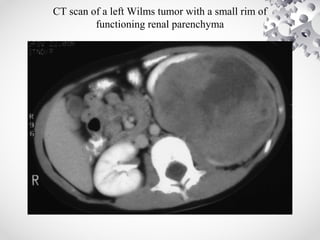

CT scan of a left Wilms tumor with a small rim of

functioning renal parenchyma

• CT SCAN: helpsto determine origin of the tumor, lymph node involvement, B/L kidney involvement, invasion into major vessels (IVC), and liver metastases. CT chest to rule out lung metastasis.

CT scan ofa left Wilms tumor with a small rim of functioning renal parenchyma